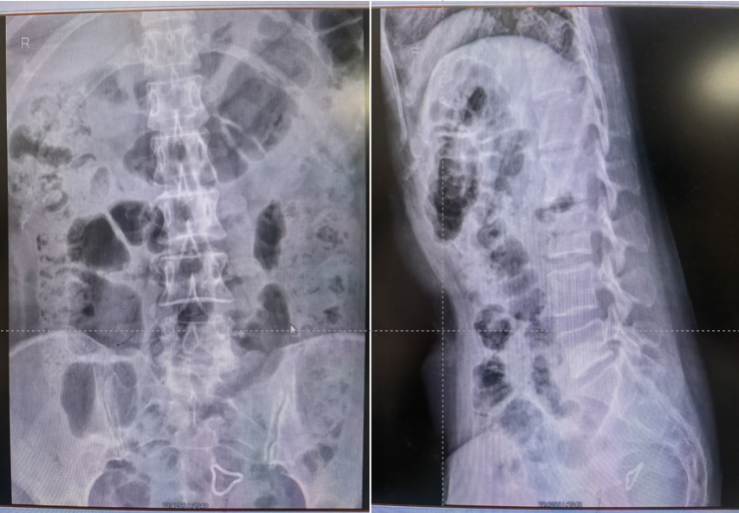

这次手术的主角是一位45岁的姐姐,她被“反复腰痛+左下肢放射性疼痛、麻木”困扰了4个月,实在遭不住才来医院。检查发现是L5-S1腰椎间盘突出,神经遭压得梆紧,保守治疗根本不管用,连日常走路、上班都成了难题。传统手术虽然能解决问题,但“大刀阔斧”的创伤和漫长的恢复期想想就脑壳痛!为了让姐姐少受罪、快康复,咱们多学科团队反复评估后,决定用国际前沿的PEID微创手术“精准打击”!